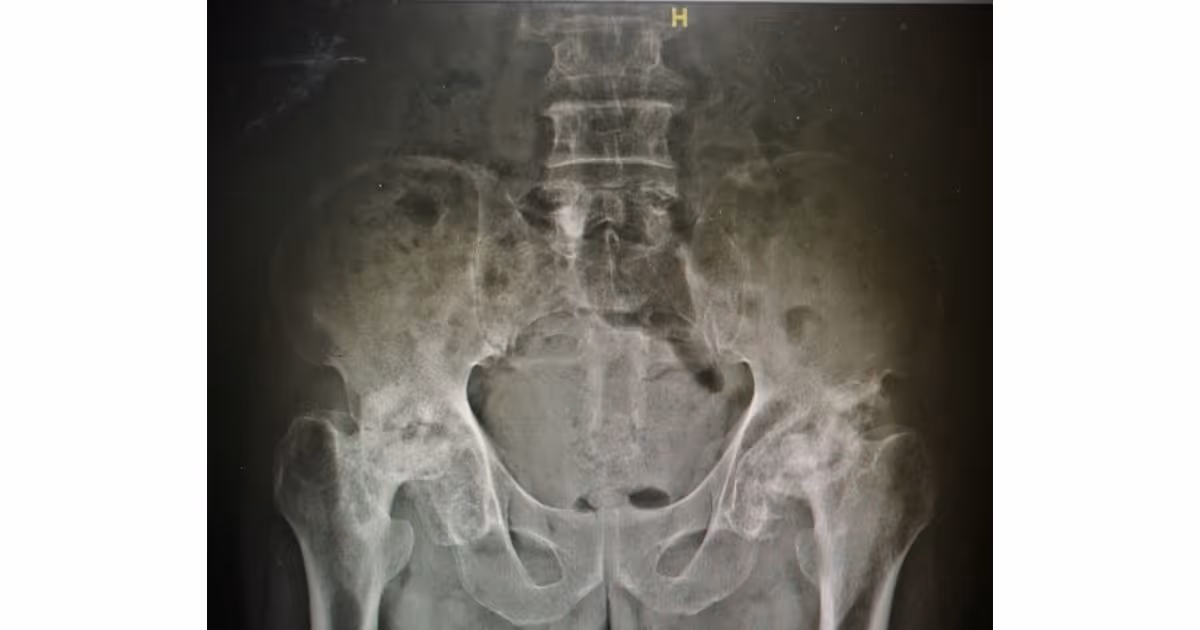

When the blood supply to the femoral head is disrupted, avascular necrosis ensues. The hard strong femoral head soften and collapse from the weight bearing.

When the blood supply to the femoral head is disrupted, avascular necrosis ensues. The hard strong femoral head soften and collapse from the weight bearing. The smooth articular surface of the femoral head become roughened leading to hip osteoarthritis.

Your doctor will ask about your medical condition, perform a physical exam, and order X-ray of both hip joints. In some cases, MRI may be required because early-stage disease may not be detectable by regular X-ray imaging.